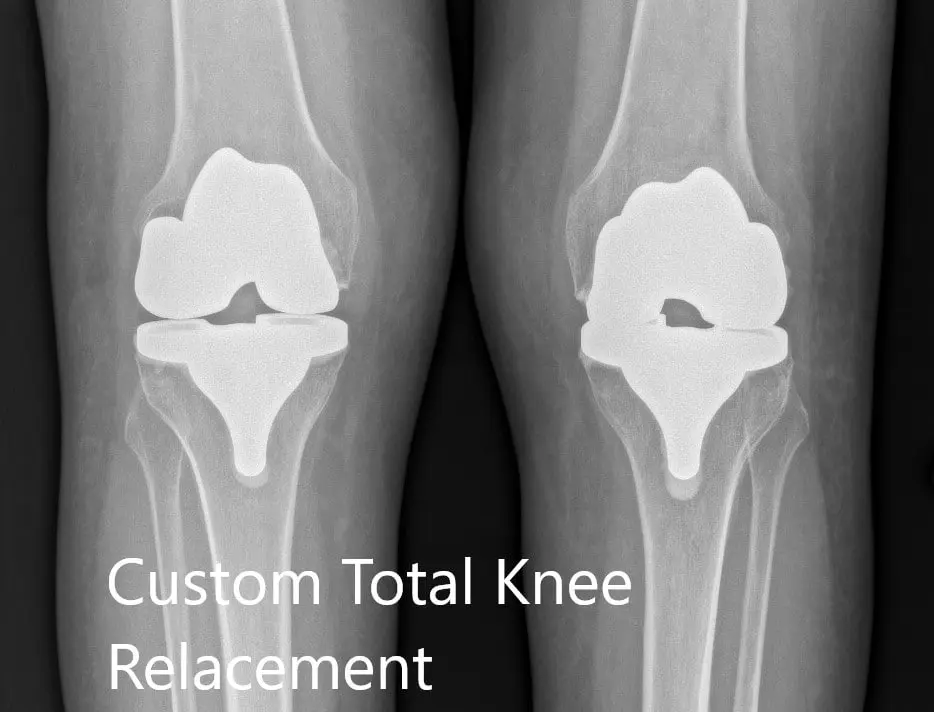

Postoperative X-ray showing the AP view of both knees